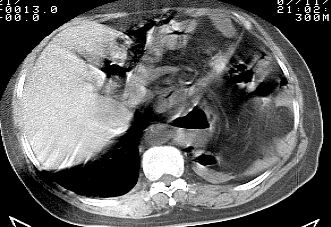

标题: CT10753:女, 64岁 隔疝 [打印本页]

标题: CT10753:女, 64岁 隔疝

女, 64岁 三十年前胸部外伤史, 间断胸闷,

典型左侧膈疝,疝出物为胃和大网膜,纵隔右移

同意左侧膈疝,不过,有过外伤史,左肺有受压征象,同时有胸膜增厚。

30年了,病人够痛苦的了,应该做修补术。

时间这么长,也没有做特殊处理 ,不多见。